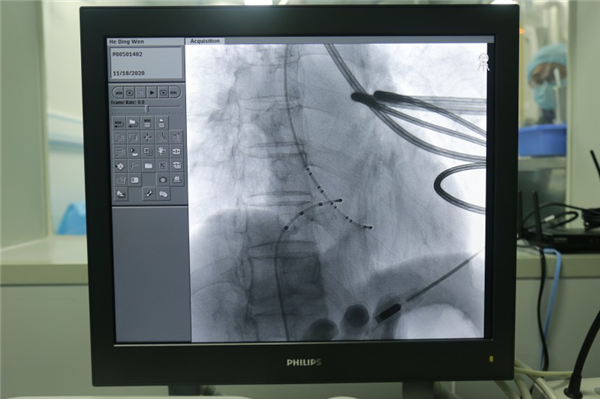

电生理团队术前制定了缜密的手术预案,由主任医师张定宝、副主任医师易蓉在该院介入导管室借助刚引进配置的飞利普血管造影机行射频消融术。在2个小时左右时间内放置好右心室电极,冠状窦电极,希氏电极,做心内电生理检查提示AⅤNRT(房室结折返性心动过速)。置入消融电极,行射频消融成功,观察15分钟后反复药物刺激及电刺激均无复发,最终消融成功,患者安全返回病房。